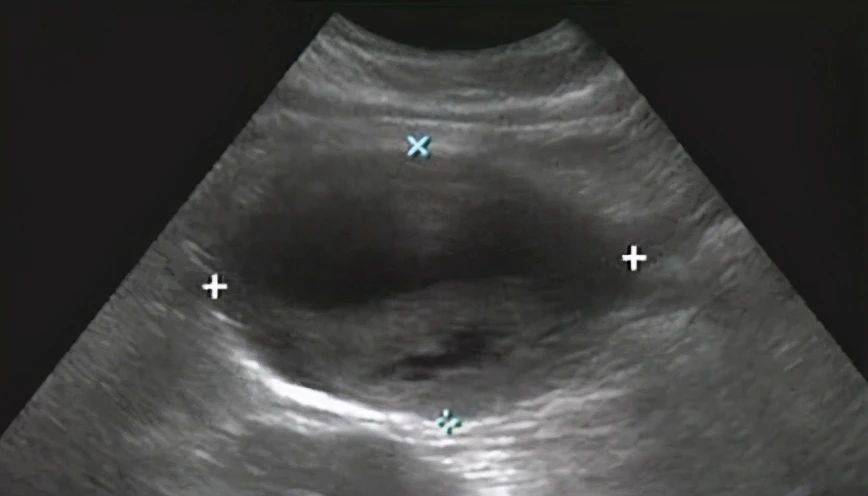

真性动脉瘤:最为常见 , 由许多因素引起 , 包括动脉粥样硬化、马凡综合征、感染、炎症等 。 真正的主动脉瘤仍然具有全厚度的血管结构 , 即外膜、中膜和内膜,为动脉壁全层扩张膨大的动脉瘤 , 血管壁仍完整 。 按压膨大处有搏动感 。

血流呈花色涡流 , 腔内低回声考虑为血栓形成 , 超声提示:真性动脉瘤伴血栓形成 。